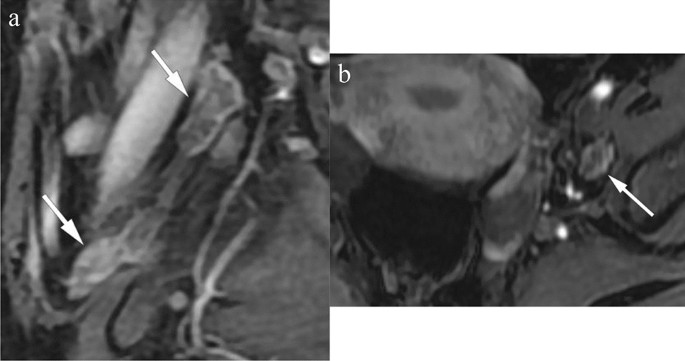

The baseline tumor size was determined as the maximum tumor diameter measured on the pretreatment MRI. The three dimensions of the lymph node with the largest short diameter were measured, and the signal intensity after Gadolinium administration was assessed, as shown in Fig. 2. The lymph node was considered radiologically positive if it met one of the following criteria: (1) a shortest diameter of more than 8 mm10; (2) ring enhancement showing necrosis inside the lymph node.

Baseline lymph node measurement and signal intensity evaluation after contrast administration. (a) sagittal contrast-enhanced T1WI shows clusters of lymph nodes in the obstrutor area (arrows), the cranial-caudal and antero-posterior diameter of the largest lymph node was measured as 25.8 and 13.3mm (upper arrow). Central necrosis was identified in it. (b) Axial contrast-enhanced T1WI shows the transverse diameter of the largest obstrutor lymph node is 9.36mm (arrow). This patient was identified as with positive radiological lymph node.